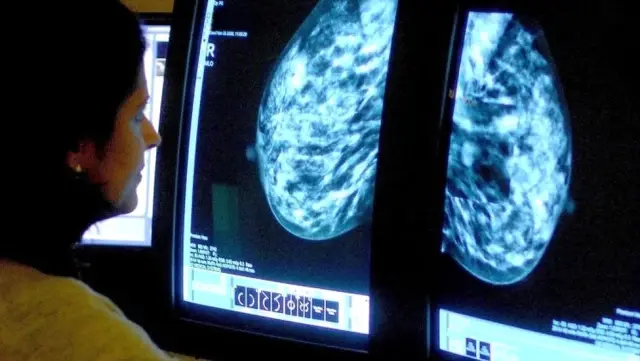

Kapsamlı yeni bir araştırmaya nazaran bayanlarda menopoza yönelik hormon tedavisinin göğüs kanseri açısından yarattığı ek risk, tedavi bırakıldıktan sonra 10 yılı aşkın müddet devam ediyor.

Araştırmayı yürüten Oxford Üniversitesi’nden bilim insanları, hormon tedavisinin yol açtığı göğüs kanseri riskinin daha evvel düşünüldüğünden iki kat yüksek olduğu sonucuna vardı.

Buna bağlı olarak, Batılı ülkelerde 1990’lı yıllarda menopoza yönelik hormon tedavisinin yol açtığı göğüs kanseri hadiselerinin bir milyon civarında olduğu iddia ediliyor.